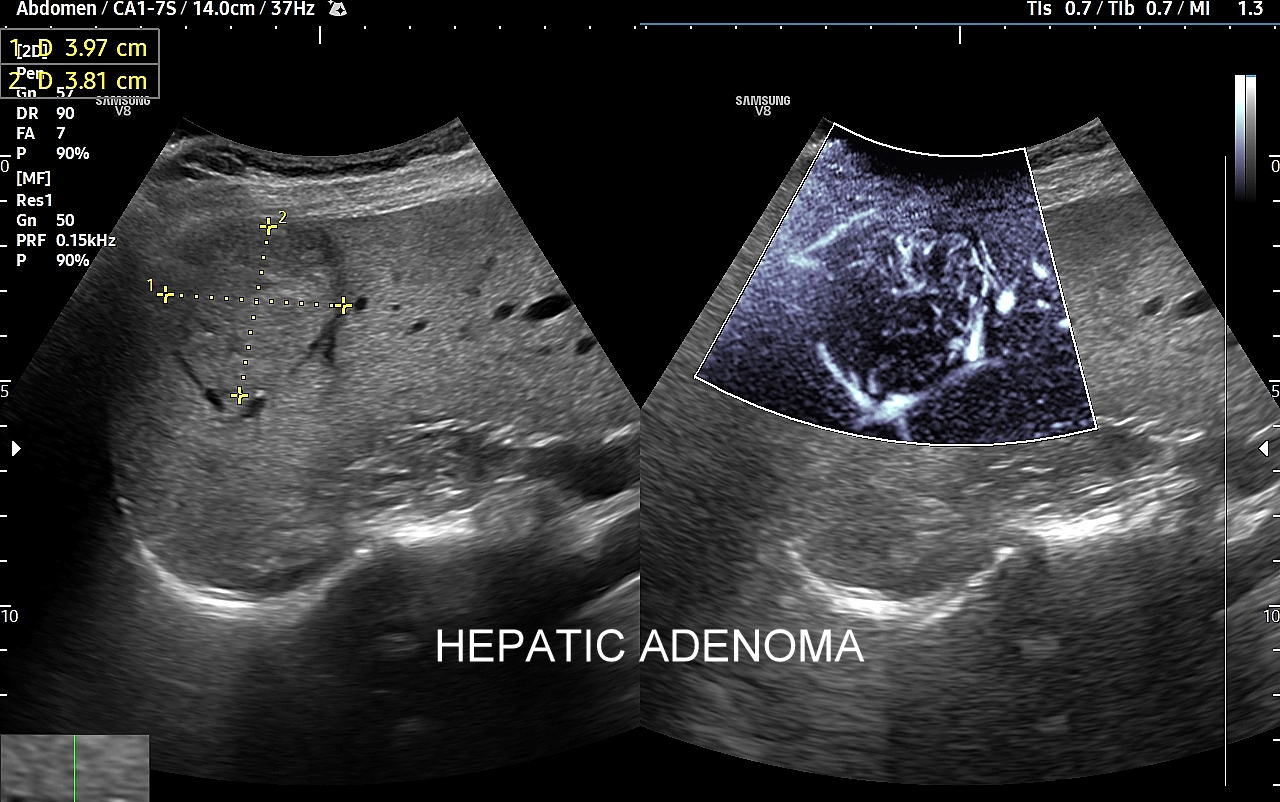

Rozwinięciem standardowego badania USG jamy brzusznej jest badanie multiparametryczne MPUS (ang. multiparametric ultrasound), w ramach którego wykorzystuje się różnorodne, nowoczesne modalności sonograficzne, takie jak tryby mikrounaczynienia MVI, B-flow, elastografię, ilościową ocenę stłuszczenia wątroby QUS, czy tryb Dopplera spektralnego, a to wszystko w celu uzyskania dodatkowej oceny funkcjonalnej i biologicznej struktur, narządów oraz tkanek jamy brzusznej. Obrazowanie MPUS niejednokrotnie poprawia także wizualną ocenę narządów wewnętrznych, czego przykładem jest zastosowanie trybu MVI w ramach bezkontrastowej angiografii sonograficznej naczyń oraz w ocenie guzów nerek. Klasycznymi i najczęstszymi zastosowaniami badania MPUS są jednakże funkcjonalna ocena wątroby w kierunku stłuszczenia, zwłóknienia, zapalenia i nadciśnienia wrotnego, a także ocena żywotności i funkcji nerek.

• Możliwość rozszerzenia zakresu badania USG w razie wystąpienia konieczności. Praktycznymi przykładami są zastosowanie trybu MVI w przypadku wykrycia guzka w nerce, czy przeprowadzenie badania elastograficznego i dopplerowskiego w wypadku stwierdzenia nieprawidłowego obrazu wątroby.